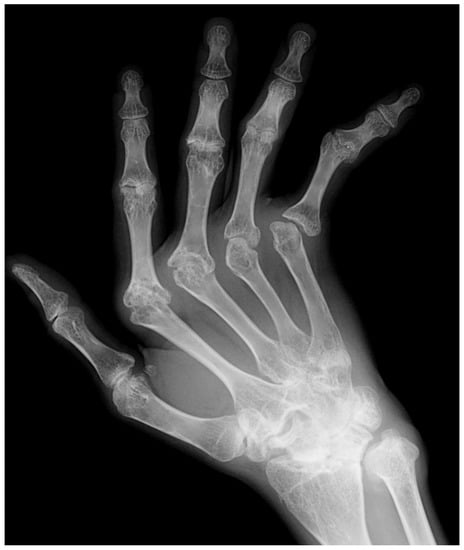

4. Rheumatoid Arthritis